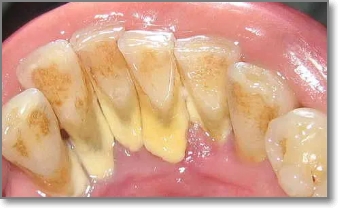

치석은 오랜 시간 쌓이면서 잇몸과 치아 사이를 가리고 있던 돌 같은 물질입니다. 이 치석이 갑자기 떨어지거나 스케일링으로 제거되면 그동안 가려져 있던 치아뿌리나 잇몸 틈이 드러나면서 공간(구멍)이 생긴 것처럼 보일 수 있어요.

특히 아래와 같은 경우라면 구멍이 더 쉽게 생길 수 있습니다:

- 오랫동안 스케일링을 하지 않아 잇몸이 치석에 눌려 있던 경우

- 치주염이 진행되어 잇몸 뼈가 약해진 상태

- 치아 사이 틈이 넓은 구조

- 치석 제거 후 제대로 된 관리가 안 된 경우